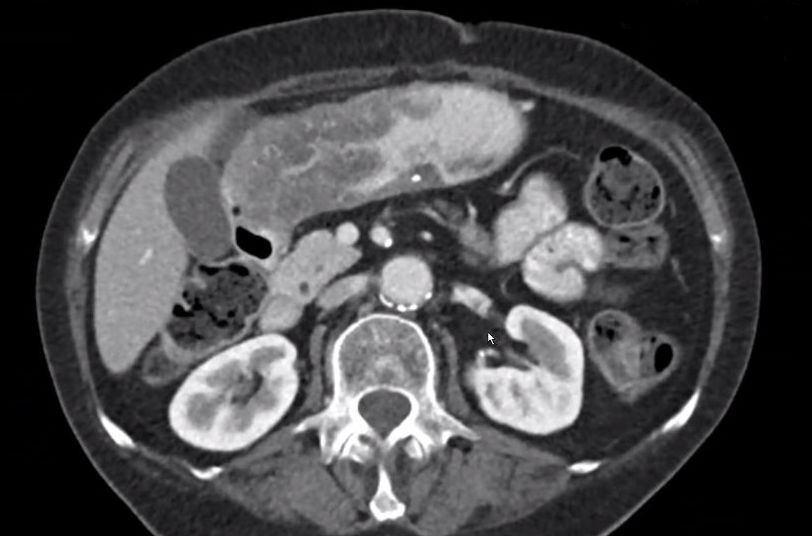

| Magenantrum | 54-jährige Frau mit obstruierendem Magenantrumkarzinom. ![]() |

|||